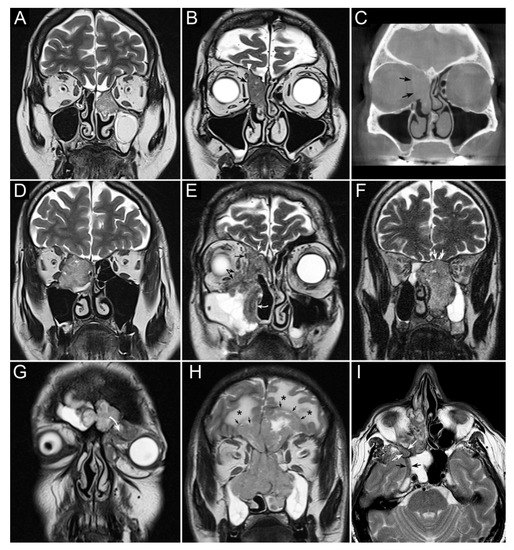

- Maroldi, R.; Borghesi, A.; Ravanelli, M.; Golemi, S.; Farina, D. The role of morphologic and functional imaging in pretreatment assessment. Adv. Otorhinolaryngol. 2020, 84, 28–45. [Google Scholar]

- Maroldi, R.; Farina, D.; Battaglia, G.; Maculotti, P.; Nicolai, P.; Chiesa, A. MR of malignant nasosinusal neoplasms frequently asked questions. Eur. J. Radiol. 1997, 24, 181–190. [Google Scholar] [CrossRef]

- Ferrari, M.; Migliorati, S.; Tomasoni, M.; Crisafulli, V.; Nocivelli, G.; Paderno, A.; Rampinelli, V.; Taboni, S.; Schreiber, A.; Mattavelli, D.; et al. Sinonasal cancer encroaching the orbit: Ablation or preservation? Oral Oncol. 2021, 114, 105185. [Google Scholar] [CrossRef] [PubMed]

- Yan, C.H.; Tong, C.C.L.; Penta, M.; Patel, V.S.; Palmer, J.N.; Adappa, N.D.; Nayak, J.V.; Hwang, P.H.; Patel, Z.M. Imaging predictors for malignant transformation of inverted papilloma. Laryngoscope 2019, 129, 777–782. [Google Scholar] [CrossRef] [PubMed]